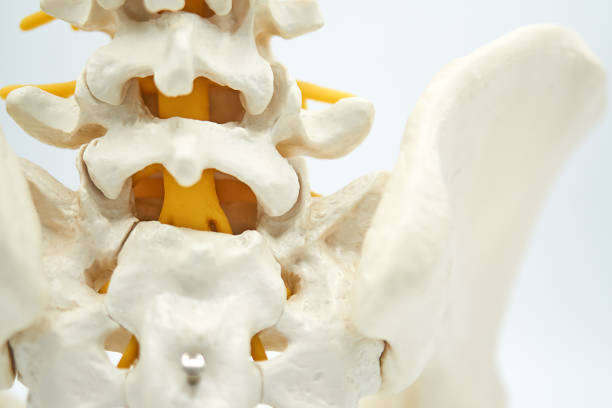

처장관절은 천골(엉치뼈), 장골(엉덩이뼈)가 만나는 부위로 외부 충격 혹은 골반이 힘을 주며 불편한 자세로 일어나거나 한쪽으로 체중이 쏠리는 잘못된 자세로 인하여 천장관절 주변으로 조직이나 인대 등에서 통증을 유발하는데 심할 경우 계단 오르내리는 것 자체도 어려워 질 수 있습니다.